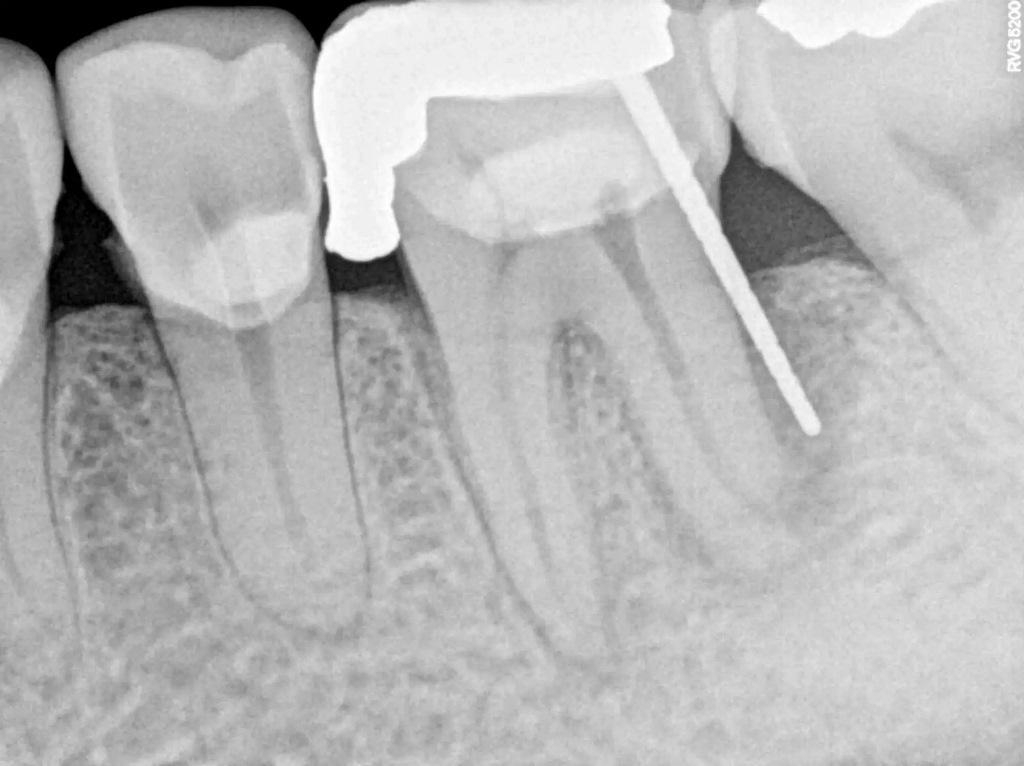

50-летний пациент с системным заболеванием, не вызывающим сопутствующих заболеваний, обратился с основной жалобой на боль при жевании. Он сообщил, что шесть месяцев назад ему была проведена прямая реставрация первого коренного зуба левой нижней челюсти. При клиническом и рентгенологическом обследовании была обнаружена большая, чрезмерно растянутая пломба из амальгамы II класса, а также J-образное просвечивание дистальной части зуба (фото 1). Также наблюдались дистально ориентированная буккальная припухлость и признаки окклюзионного износа, характерные для бруксизма зубных рядов. Зуб болезненно реагировал на перкуссию и отрицательно реагировал на электрические и тепловые стимулы. При зондировании в области абсцесса был выявлен изолированный карман диаметром 9 мм (фото 2). У зуба был диагностирован некроз пульпы и периапикальный абсцесс, а также подозрение на VRF. Для подтверждения предполагаемого диагноза была подготовлена полость доступа под изоляцией коффердамом и под стоматологическим операционным микроскопом. Когда предыдущая реставрация была удалена, на дистальной стороне дна пульпы при увеличении в 10 раз была обнаружена линия продольной трещины.